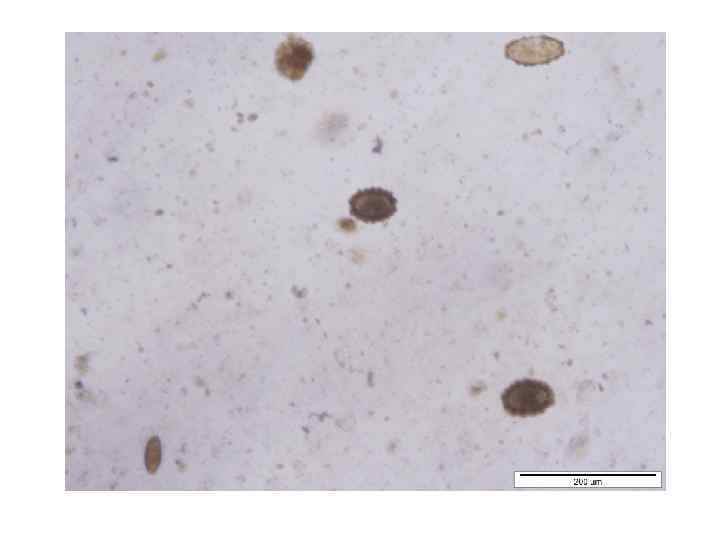

Причины ложноотрицательных результатов исследования «кала на яйца глист» 2. Аналитические причины: а) В лабораториях часто анализируют обычный нативный толстый мазок кала. Методики, предусматривающие обесцвечивание (Kato-Katz) или флотацию (Mc. Master), не используются.